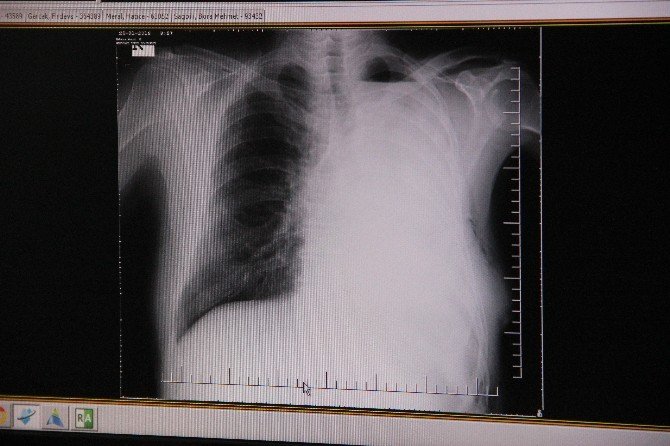

Konya'da akciğer kanseri olan 74 yaşındaki bir kişinin kalp zarı açılarak yapılan ameliyat sonrasında sol akciğeri tamamen alındı.

Konya'da çiftçilikle uğraşan 74 yaşındaki Yusuf Erkoca 15 gün önce ağzından gelen kan üzerine hastaneye gitti. Hastanede yapılan muayene sonrasında Erkoca akciğer kanseri olduğunu öğrendi. Gerçekleştirilen tetkikler sonucunda ameliyata alınan Yusuf Erkoca'nın kanserli olan sol akciğeri kalp zarı açılarak tamamen alındı.

Medicana Konya Hastanesi Göğüs Cerrahisi Operatör Doktor Serdar Özkan, yapılan ameliyat hakkında bilgiler vererek, "74 yaşındaki akciğer kanseri nedeniyle tarafımıza başvuran hastanın gerekli tetkikleri yapıldıktan sonra ameliyat planlaması gerçekleştirildi. Kanser kalp zarına yayıldığı için ameliyat esnasında kalbin zarı açılarak gerekli cerrahi müdahale kalp zarının içinden gerçekleştirildi. Normal akciğer kanseri hastalarında akciğerin bir kısmı ya da tamamı alınabilir. Bu tür ameliyatlar sıklıkla yapılmaktadır. Ancak hastamızda olduğu gibi kalp zarına yayılan tümörlerde daha genişletilmiş cerrahi yapılmaktadır. Bu tür olgular ender görülmektedir. Bu ender olgulardan biri olan 74 yaşındaki hastamızın operasyonu merkezimizde başarıyla gerçekleştirildi" dedi.